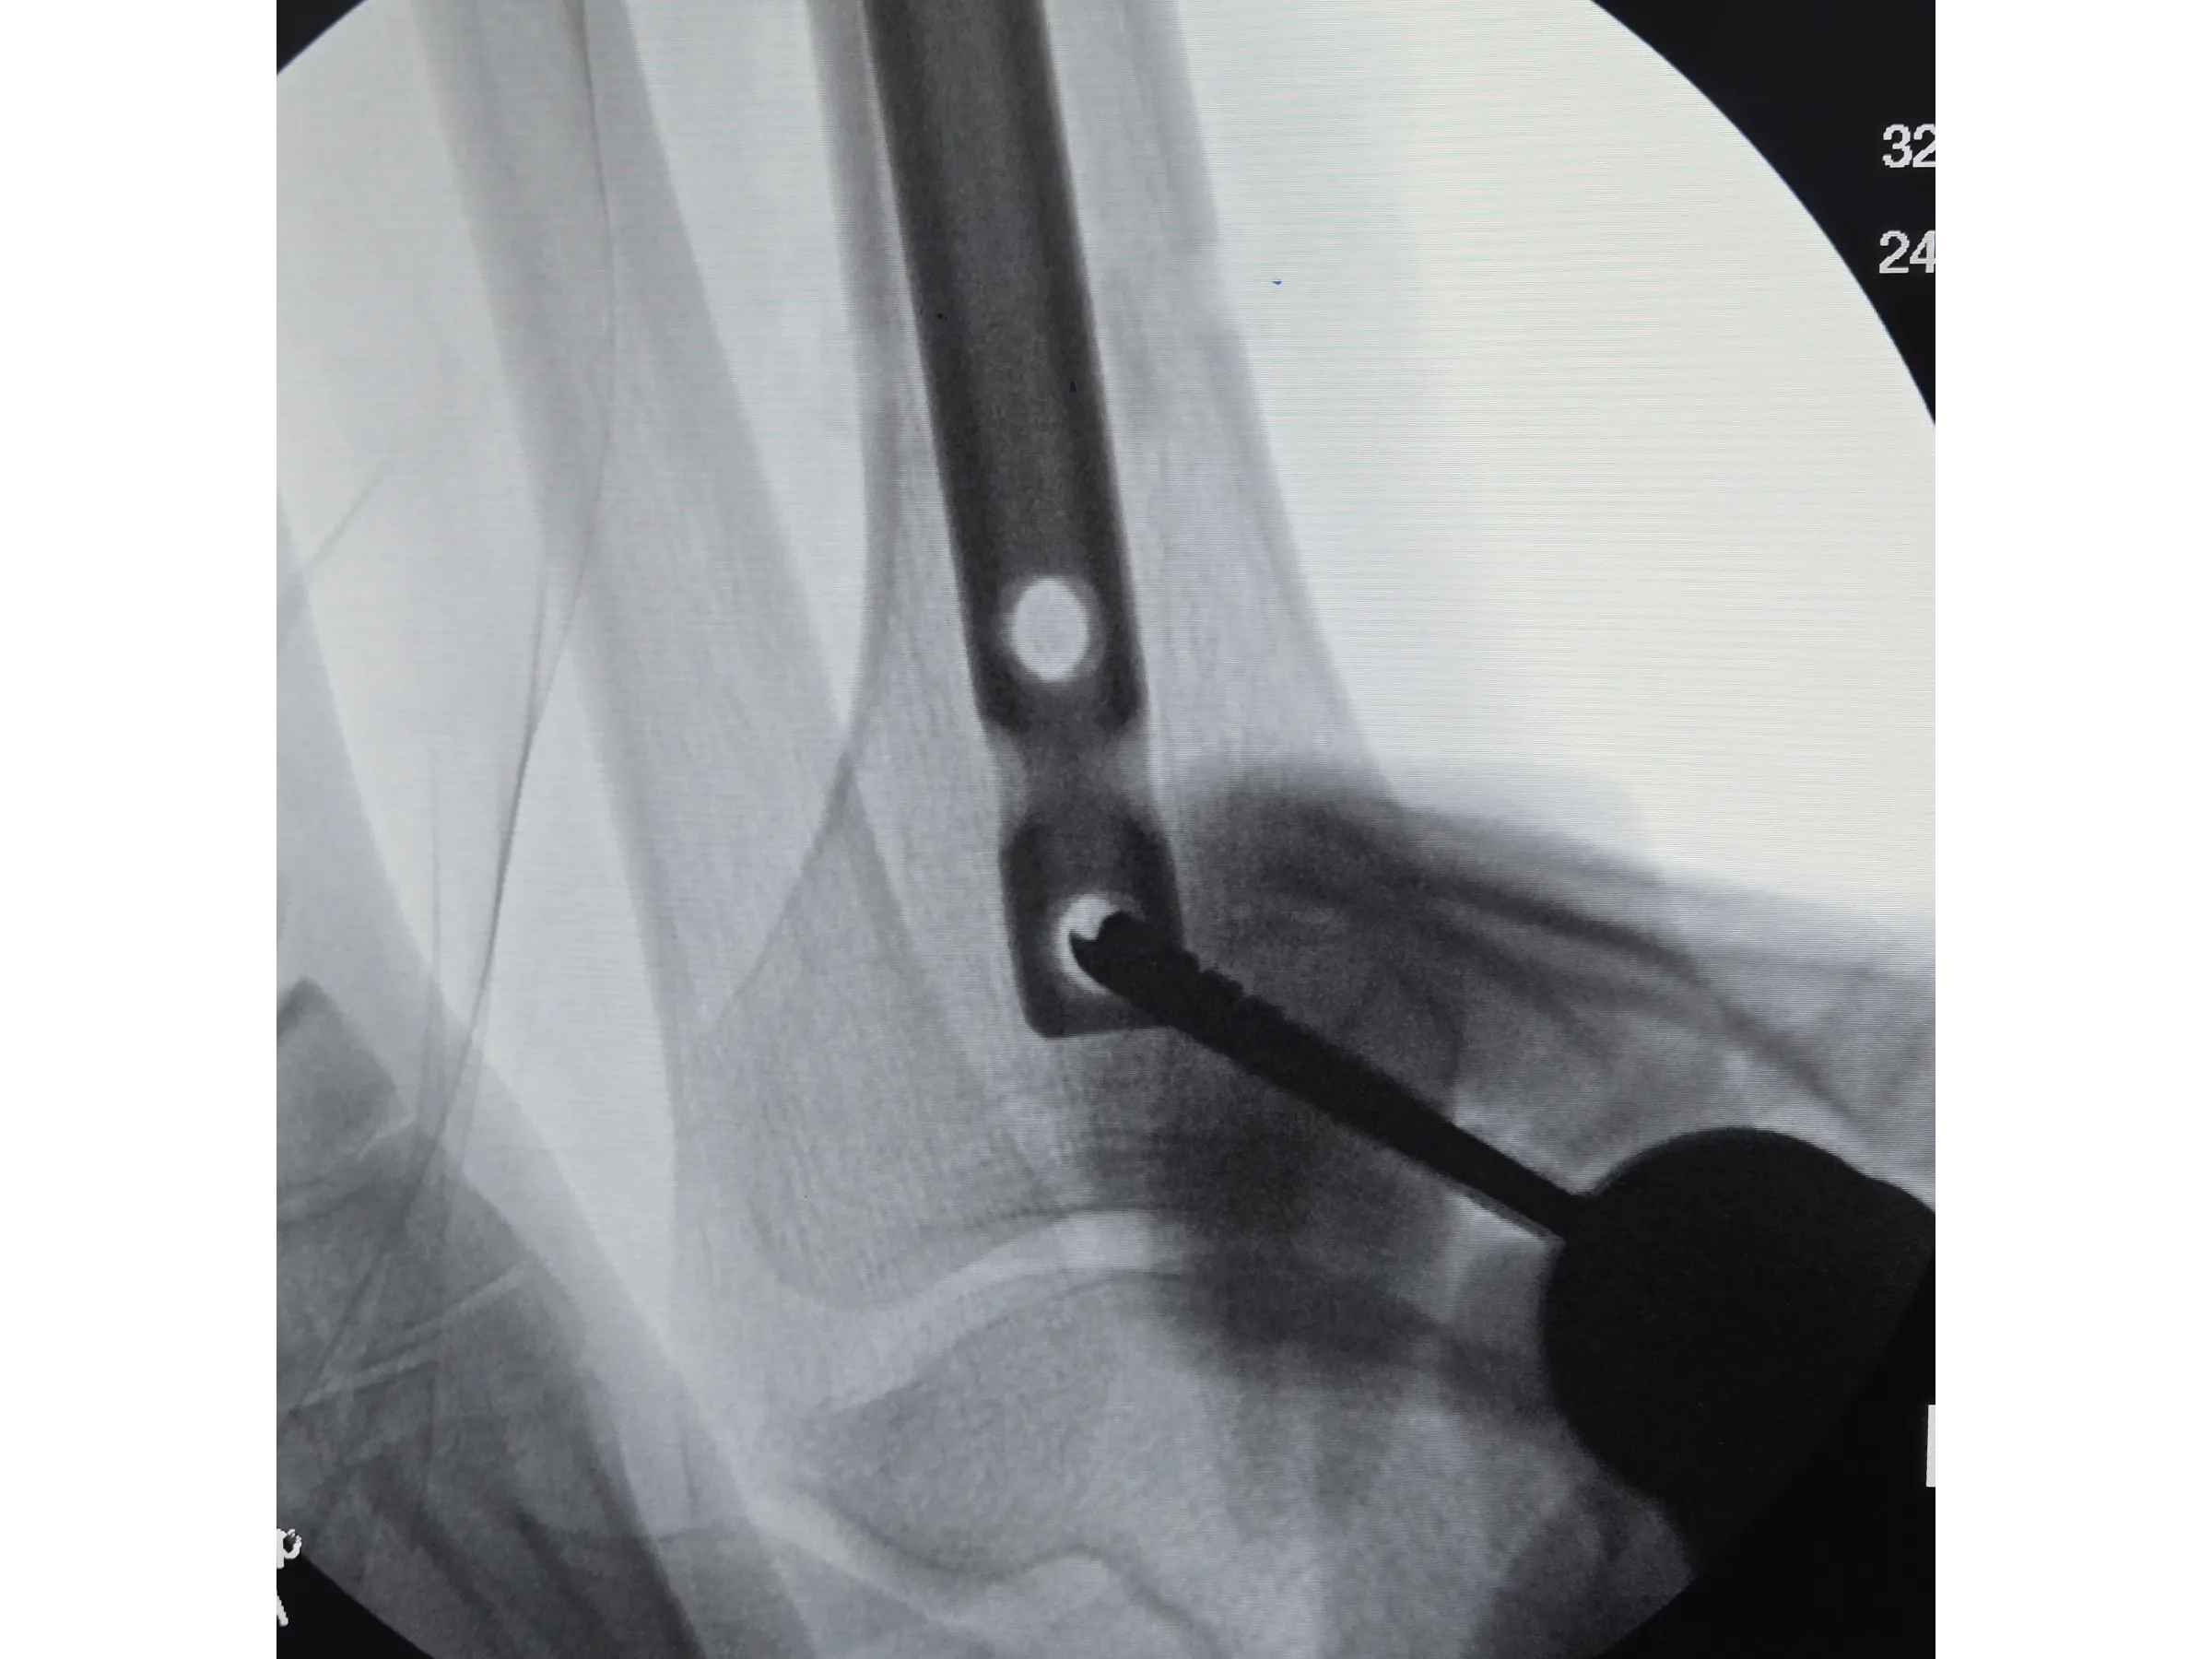

- Mensuração correta e fresagem adequada do canal medular;

- Proteção Tecidual Durante Brocagem: Uso adequado do protetor de partes moles para evitar lesões tendíneas e da cortical anterior;

- Fresagem Precisa do Canal Medular: Parâmetros para escolha do diâmetro ideal e preparo do canal sem risco de fissuras;

- Bloqueios Proximais e Distais Minimamente Invasivos: Execução de bloqueios cruzados e distais com pequenos portais e controle por intensificador;